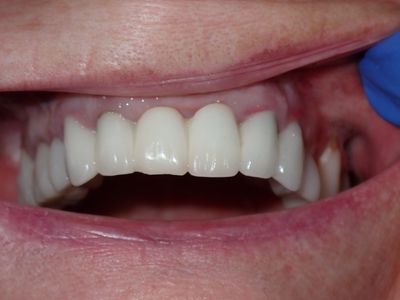

NSankhyan - immediate 13, impls 1121 and 25 with grafting

13 exo, loss of labial plate, implant placed buccal region grafted with sticky bone and collagen membrane soaked in prf fluid. 11/21 limited Labial-palatal width of bone, ridge split to 5mm, osteotomies prepared to about 2mm, remainder with densah drills, implants placed with ample bone, buccal grafted with same sticky bone. densah drills used for apical portion of 25 implant, soft bone, implant placed